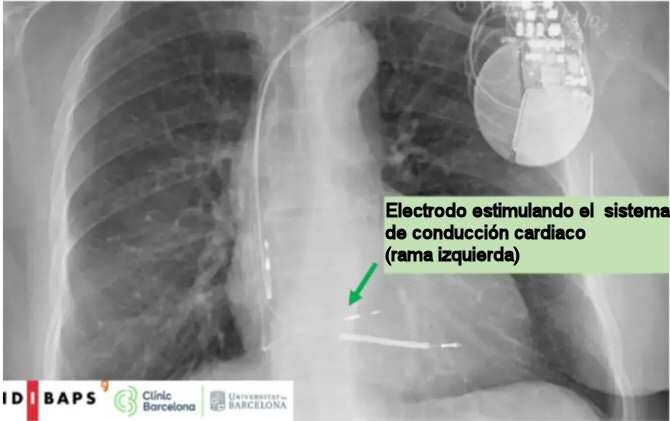

Radiografía de tórax que muestra un dispositivo de estimulación cardíaca de la rama izquierda implantado en el Hospital Clínic de Barcelona. (Imagen: IDIBAPS / Hospital Clínic de Barcelona / Universitat de Barcelona)

En cambio, la estimulación de la rama izquierda consiste en implantar un cable de estimulación directamente en el sistema de conducción natural del corazón, buscando una activación eléctrica más fisiológica y coordinada. A pesar de su creciente aplicación en la práctica clínica, hasta ahora había pocos estudios aleatorizados publicados que compararan esta técnica con la estimulación biventricular, y ninguno tenía como objetivo principal el estudio de la respuesta clínica.